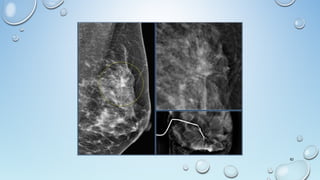

Breast Classifications

FIBRO-GLANDULAR BREAST

• Fibro-glandular

• Dense With Very Little Fat

• Females 15-30 Years Of Age

• Or 30 Years Or Older Without Children

• Pregnant Or Lactating

FIBRO-FATTY BREAST

• Fibro-fatty

• Average Density

• 50% Fat & 50% Fibro-glandular

• Women 30-50 Years Of Age

• Or Women With 3 Or More Children

FATTY BREAST

• Fatty

• Minimal Density

• Women 50 And Older

(Postmenopausal), Men And Children